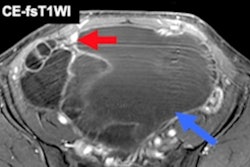

Both MRI and CT have been used for some time for staging to guide surgical planning. While MRI is used for local staging, gauging depth of endometrial invasion, cervical involvement, and local dissemination of disease in the pelvis, typically CT is used for staging the remainder of the chest, abdomen, and pelvis to look for the more advanced stages of disease. However, prediction of nodal metastasis remains challenging due to low sensitivity in normal-sized nodes, according to Rockall.

At Imperial, Rockall's group has been looking at T2 sagittal MRI to determine whether radiomic signature can identify cases at higher risk of relapse despite low-risk traditional features such as low-grade, low-stage endometrioid disease.